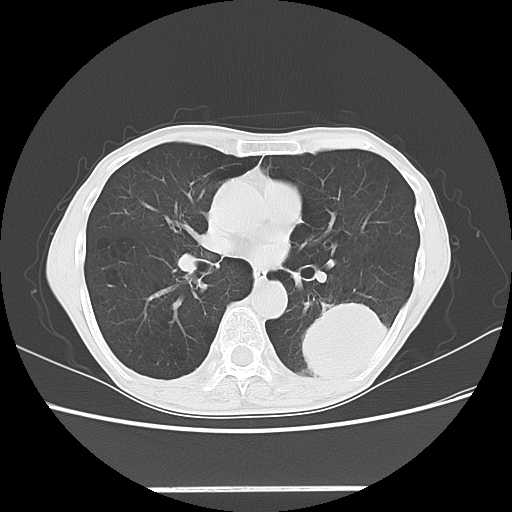

胸部

肺がん